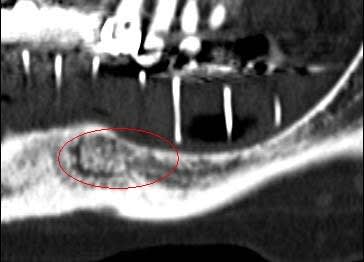

Je mets les coupes scan et tu comprendras son hésitation

Le prochain cas je propose volontiers d'être assisté par qui le veux bien, apprendre est mon plaisir, et je ne suis pas aussi buté en vrai que dans les discussions